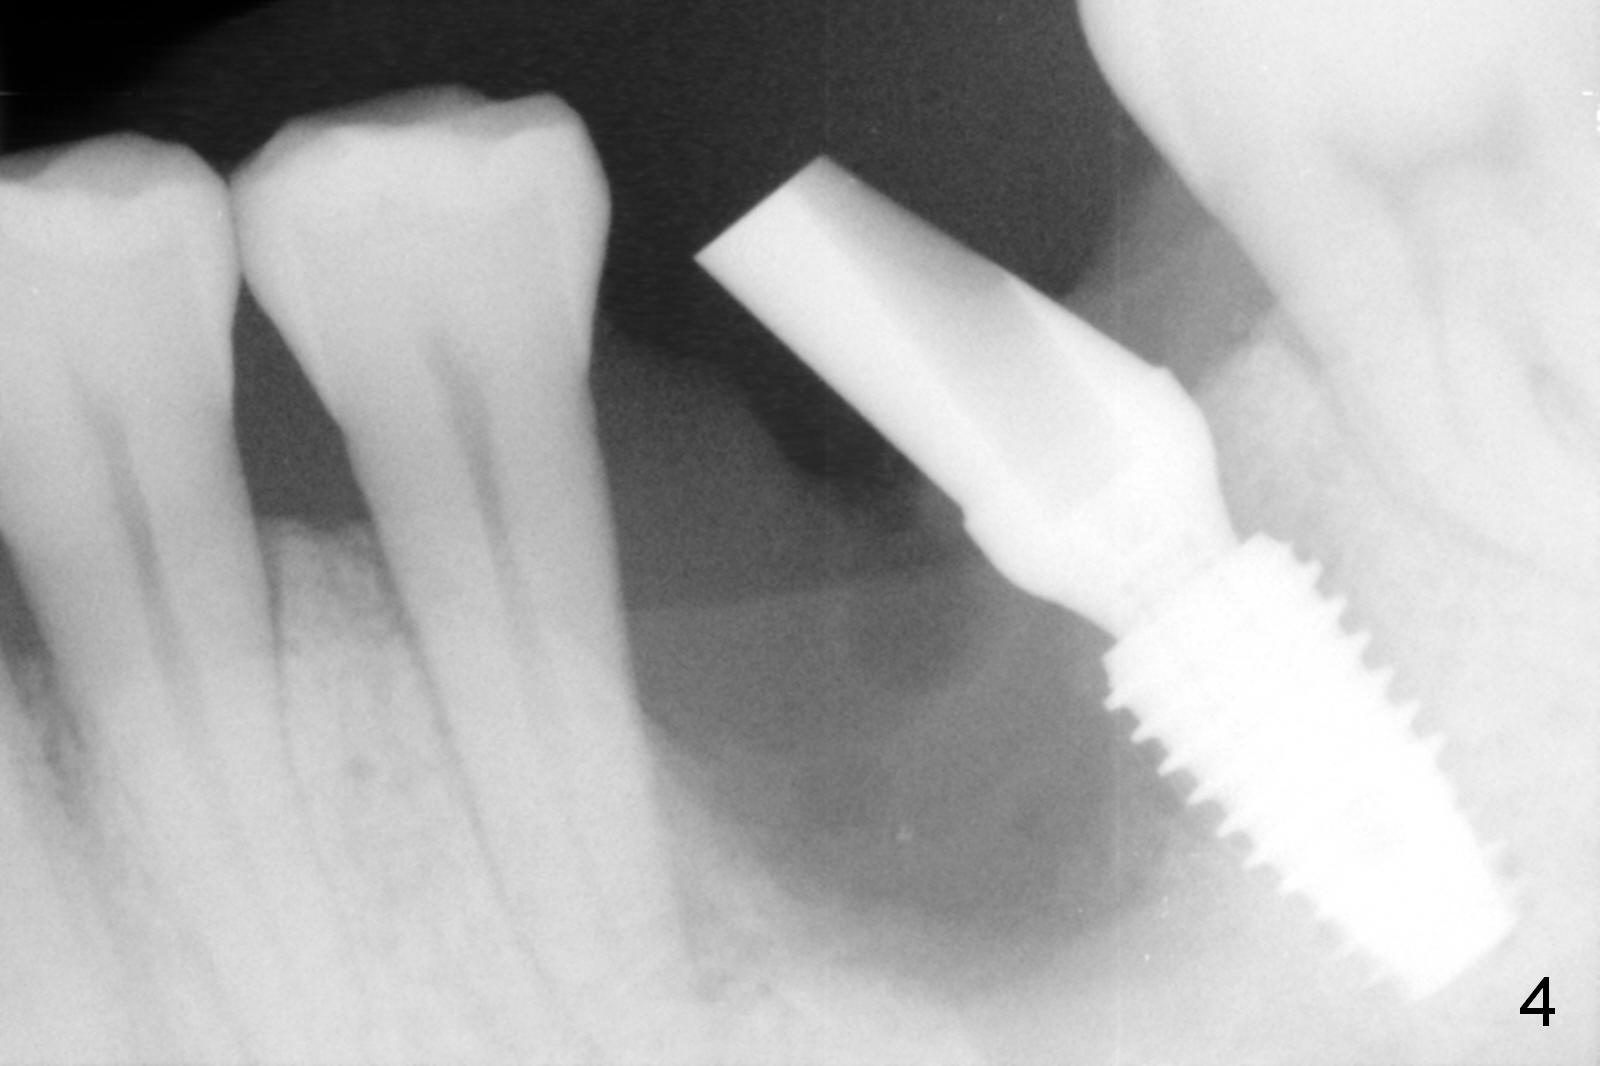

Considering the severe bone loss in the meisal socket, socket preservation is indicated if immediate implant is not feasible. Preop exam shows that the mesiobuccal gingival recession (Fig.1 MB) is not as severe as the mesiolingual one (Fig.2 ML). Because of oozing from the mesial socket, buccal envelop incision is made with flap raising to increase visibility. Probably due to periodontal infection, pain control is difficult. Osteotomy buccal to the Inferior Alveolar Canal proves to be risky. In addition, osteotomy in the mesial socket is more difficult than the distal one (Fig.3). Once the osteotomy depth is determined relative to the superior border of the Inferior Alveolar Canal (4 mm), the osteotomy depth increases by 2 mm. A 5.5x10 mm implant is placed with insertion torque ~ 35 Ncm (Fig.4); a 15 ° angled abutment (5.5 mm in diameter, 4 mm in cuff) is placed mesially. Then the abutment is turned lingually favorable for restoration (Fig.5), the remaining socket is filled with allograft/Osteogen (*) and Collagen Plug.